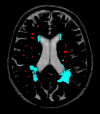

Background and purpose: Detection of longitudinal changes in white matter hyperintensities (WMH) by using visual rating scales is problematic. We compared a widely used visual rating scale with a volumetric method to study longitudinal white matter changes.

Methods: WMH were assessed with the visual Scheltens scale and a volumetric method in 100 elderly subjects aged 70-81 years for whom repetitive MR images were available with an interval of 33 (SD, 1.4) months. Reliability was determined by intraclass correlation coefficients. To examine the sensitivity of both the visual and volumetric method, we calculated Spearman rank correlations of WMH ratings and volume measurements with age.

Results: Reliability of the visual rating scale was good, whereas reliability of the volumetric measurement was excellent. For baseline measurements of WMH, we found weaker associations between WMH and age when assessed with the visual scale (r = 0.20, P = .045) than with the volumetric method (r = 0.31, P = .002). Longitudinal evaluation of WMH assessments showed regression in 26% of the subjects when analyzed with the visual rating scale against 12% of the subjects when using volumetric measurements. Compared with the visual rating, the correlation between progression in WMH and age was twice as high when using the volumetric measurement (r = 0.19, P = .062 and r = 0.39, P < .001, respectively).

Conclusion: Volumetric measurements of WMH offer a more reliable, sensitive, and objective alternative to visual rating scales in studying longitudinal white matter changes.